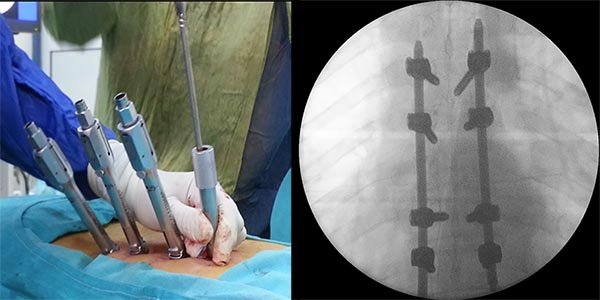

Figura 5:

Caso 8. Se realizó una estabilización percutánea T6-T10. El paciente retornó a UTI, para estabilizar su cuadro respiratorio y hemodinámico.

Este tipo de cirugía permite colocar tornillos transpediculares en forma percutánea, y unir los mismos mediante barras de titanio. Esto cumple la función de “tutor interno”, que estabiliza en forma inmediata la lesión, permitiendo la movilización, aliviando el dolor y logrando un ambiente propicio para la consolidación de las fracturas.